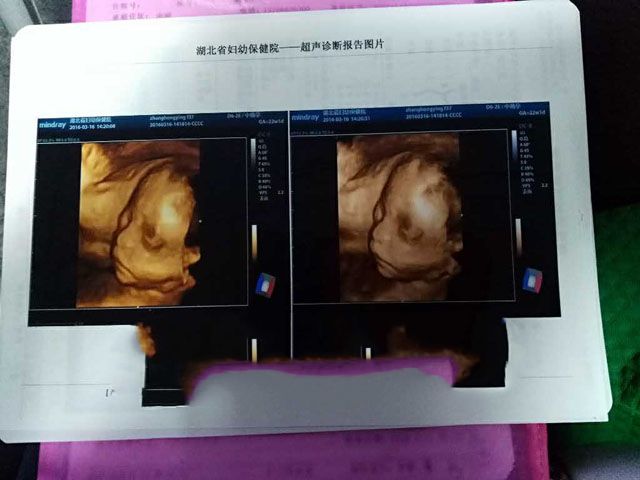

要不要看看产检记录!

2016年7月4日,孕37周,男宝宝顺利降临。